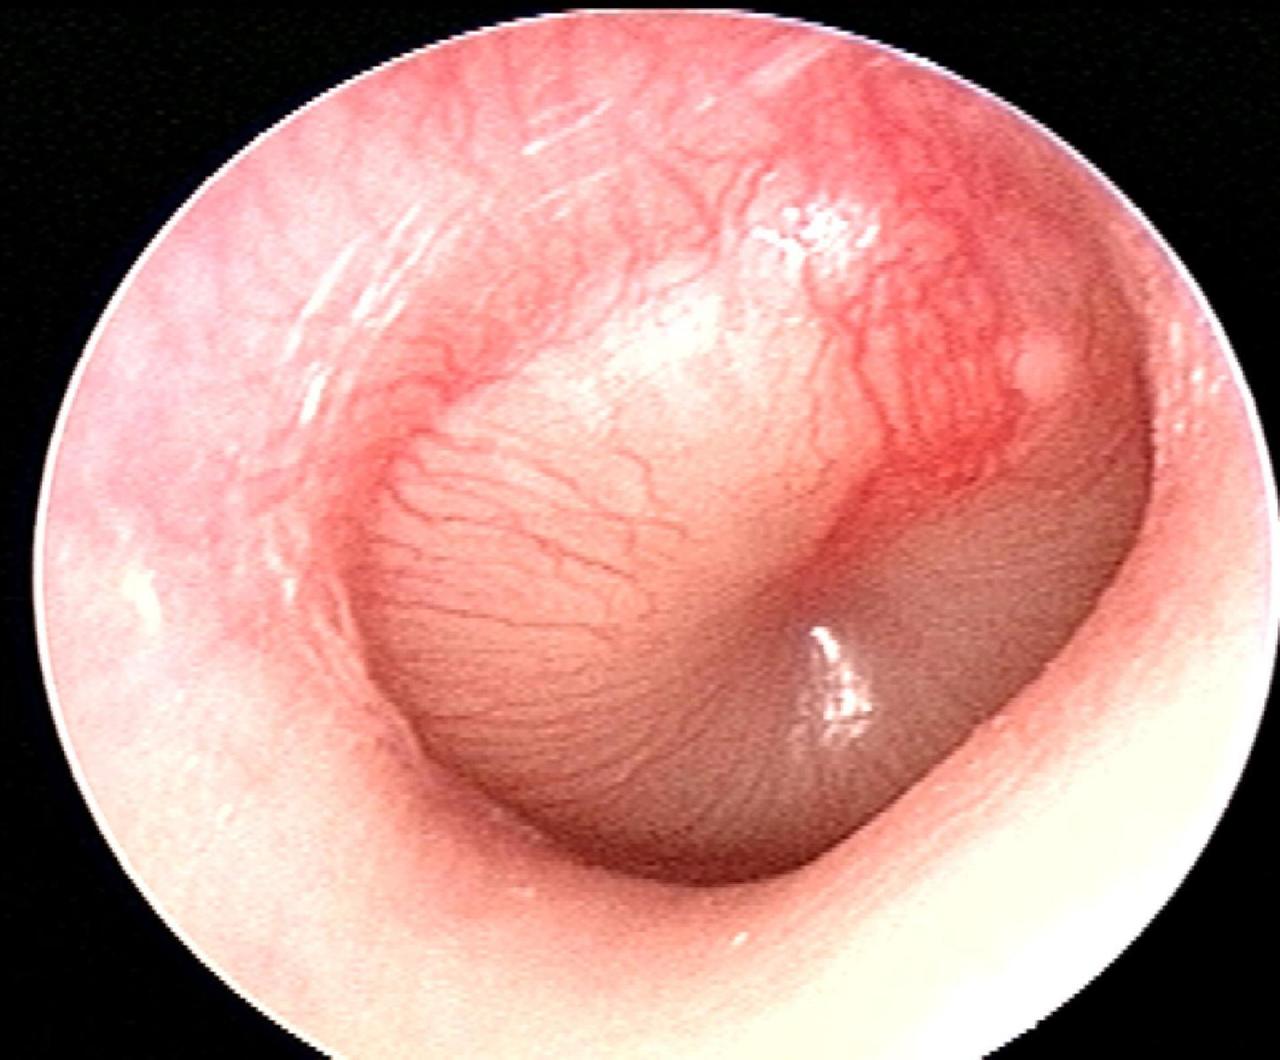

Vous faites un examen du tympan droit. Vous trouverez ci-dessous plusieurs exemples d'otoscopies. Figure 6

Figure 7

Figure 8

Figure 9

Figure 10

Question 8 - Dans le cas d’une fracture du rocher à droite, quelle(s) est (sont), parmi les otoscopies présentées ci-dessus, celle(s) qui est (sont) compatible(s) avec ce diagnostic à 24 heures du traumatisme ?

Tympan normal : la fracture peut ne pas concerner l’oreille moyenne et ne pas entraîner de saignement

Poche de rétraction avec atélectasie postérieure : il s’agit dans ce cas d’une pathologie chronique du tympan, sans rapport avec la fracture du rocher

Otite moyenne aiguë : ce n’est pas le tableau (absence de fièvre), d’autant que le délai est trop bref pour avoir une complication infectieuse

Hémotympan : visualisation d’un hématome dans l’oreille moyenne. C’est l’image typique dans le contexte de fracture du rocher

Myringite bulleuse : c’est ici une complication infectieuse avec la constitution d’une bulle intra-tympanique

Dans un contexte de fracture du rocher, soit le tympan peut être normal, soit le plus souvent il y a un saignement dans l’oreille moyenne et on constate un hémotympan. Cliniquement, l’hémotympan se comporte exactement comme une otite séromuqueuse (présence de liquide dans l’oreille moyenne), cf. les questions suivantes.